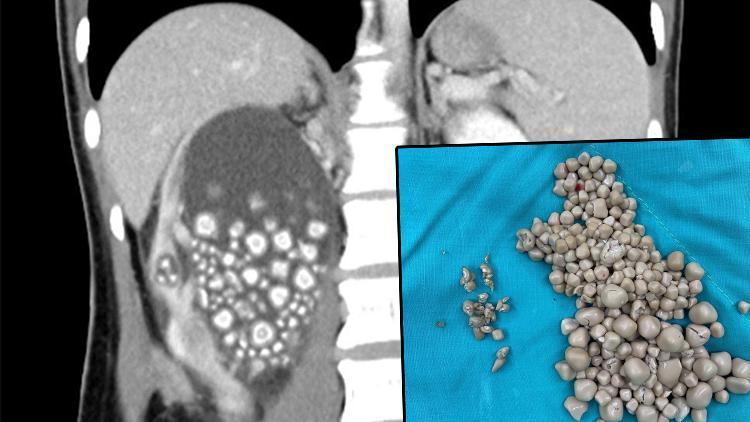

Sosyal medya bu görüntüyü konuşuyor... Böbreklerinden 300 taş çıkarıldı

Tayvan’nın Tainan şehrinde sırt ağrısı şikayetiyle hastaneye başvuran 20 yaşındaki Xiao Yu’nun böbreklerinden 300’den fazla böbrek taşı çıkarıldı.

Yapılan tetkiklerin sonucunda böbreklerinde çok sayıda böbrek taşı tespit edilen Yu acil ameliyata alındı. Başarılı geçen ameliyatın ardından Yu’nun böbreklerinden 0.5-2 cm boyutlarında 300’den fazla böbrek taşı çıkarıldı.

Ameliyatın yapıldığı Chi Mei Hastanesi tarafından yapılan açıklamada, Yu’nun su içmeyi sevmediği ve sadece şekerli içecekler ile çay tükettiği belirtildi.

Xiao Yu’nun beslenme alışkanlıklarının kötü olduğunu vurgulayan Chi Mei Hastanesi'ndeki doktorlar ise, Tayvanlılara daha sağlıklı gıdalar tüketmeleri ve bol bol su içmeleri konusunda uyarılarda bulundu.

Öte yandan, Chi Mei Hastanesi Ürologu Lin Tsai-yang, Tayvan'daki erkeklerin yüzde 14,9'unda, kadınların ise yüzde 4,3’ünde böbrek taşı oluşma ihtimali bulunduğunu kaydetti.